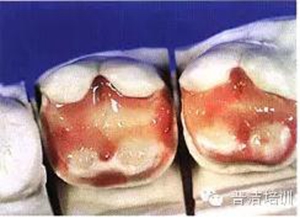

五、采用分層充填技術(shù)充填樹脂,恢復(fù)牙體原有的色澤和形態(tài)

六。用透明樹脂修復(fù)舌側(cè)壁

七、光照后,修復(fù)體完成